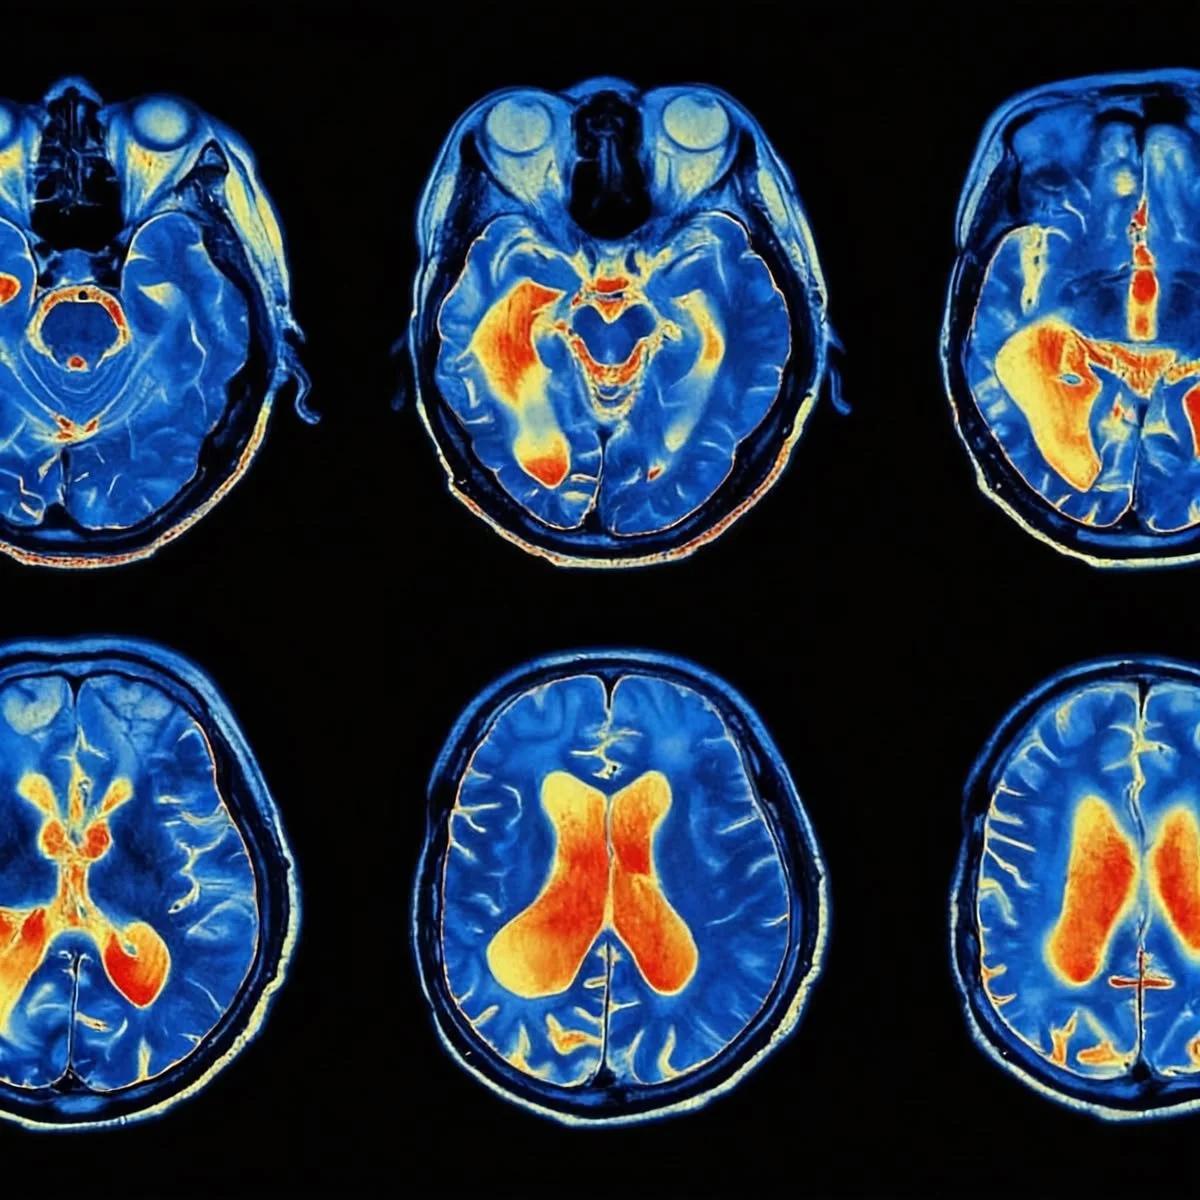

What distinguishes Iboga from almost any other substance on Earth is its unique interaction with the human brain. It doesn't just stimulate neurochemistry; it physically restructures it.

Scientific research has highlighted Iboga’s ability to stimulate the production of Glial Cell Line-Derived Neurotrophic Factor (GDNF). GDNF is a protein that acts like "fertilizer" for the brain. It promotes the survival, growth, and regeneration of neurons, particularly those in the dopaminergic system.

This surge in GDNF triggers a massive wave of neuroplasticity. It allows the brain to bypass the deeply ingrained "ruts" of habit—those neural pathways carved by years of trauma, substance abuse, or negative self-talk—and create new, healthy connections. This is the first level of recoding: clearing the physical slate of the brain.

Unlike many drugs that target one specific receptor, Ibogaine is "promiscuous" in the best sense. It interacts with NMDA, sigma, opioid (kappa and mu), and serotonin receptors simultaneously. For those struggling with chemical dependency, this "flooding" effect resets the reward system to a pre-addicted state, often eliminating withdrawal symptoms and cravings in a single session.